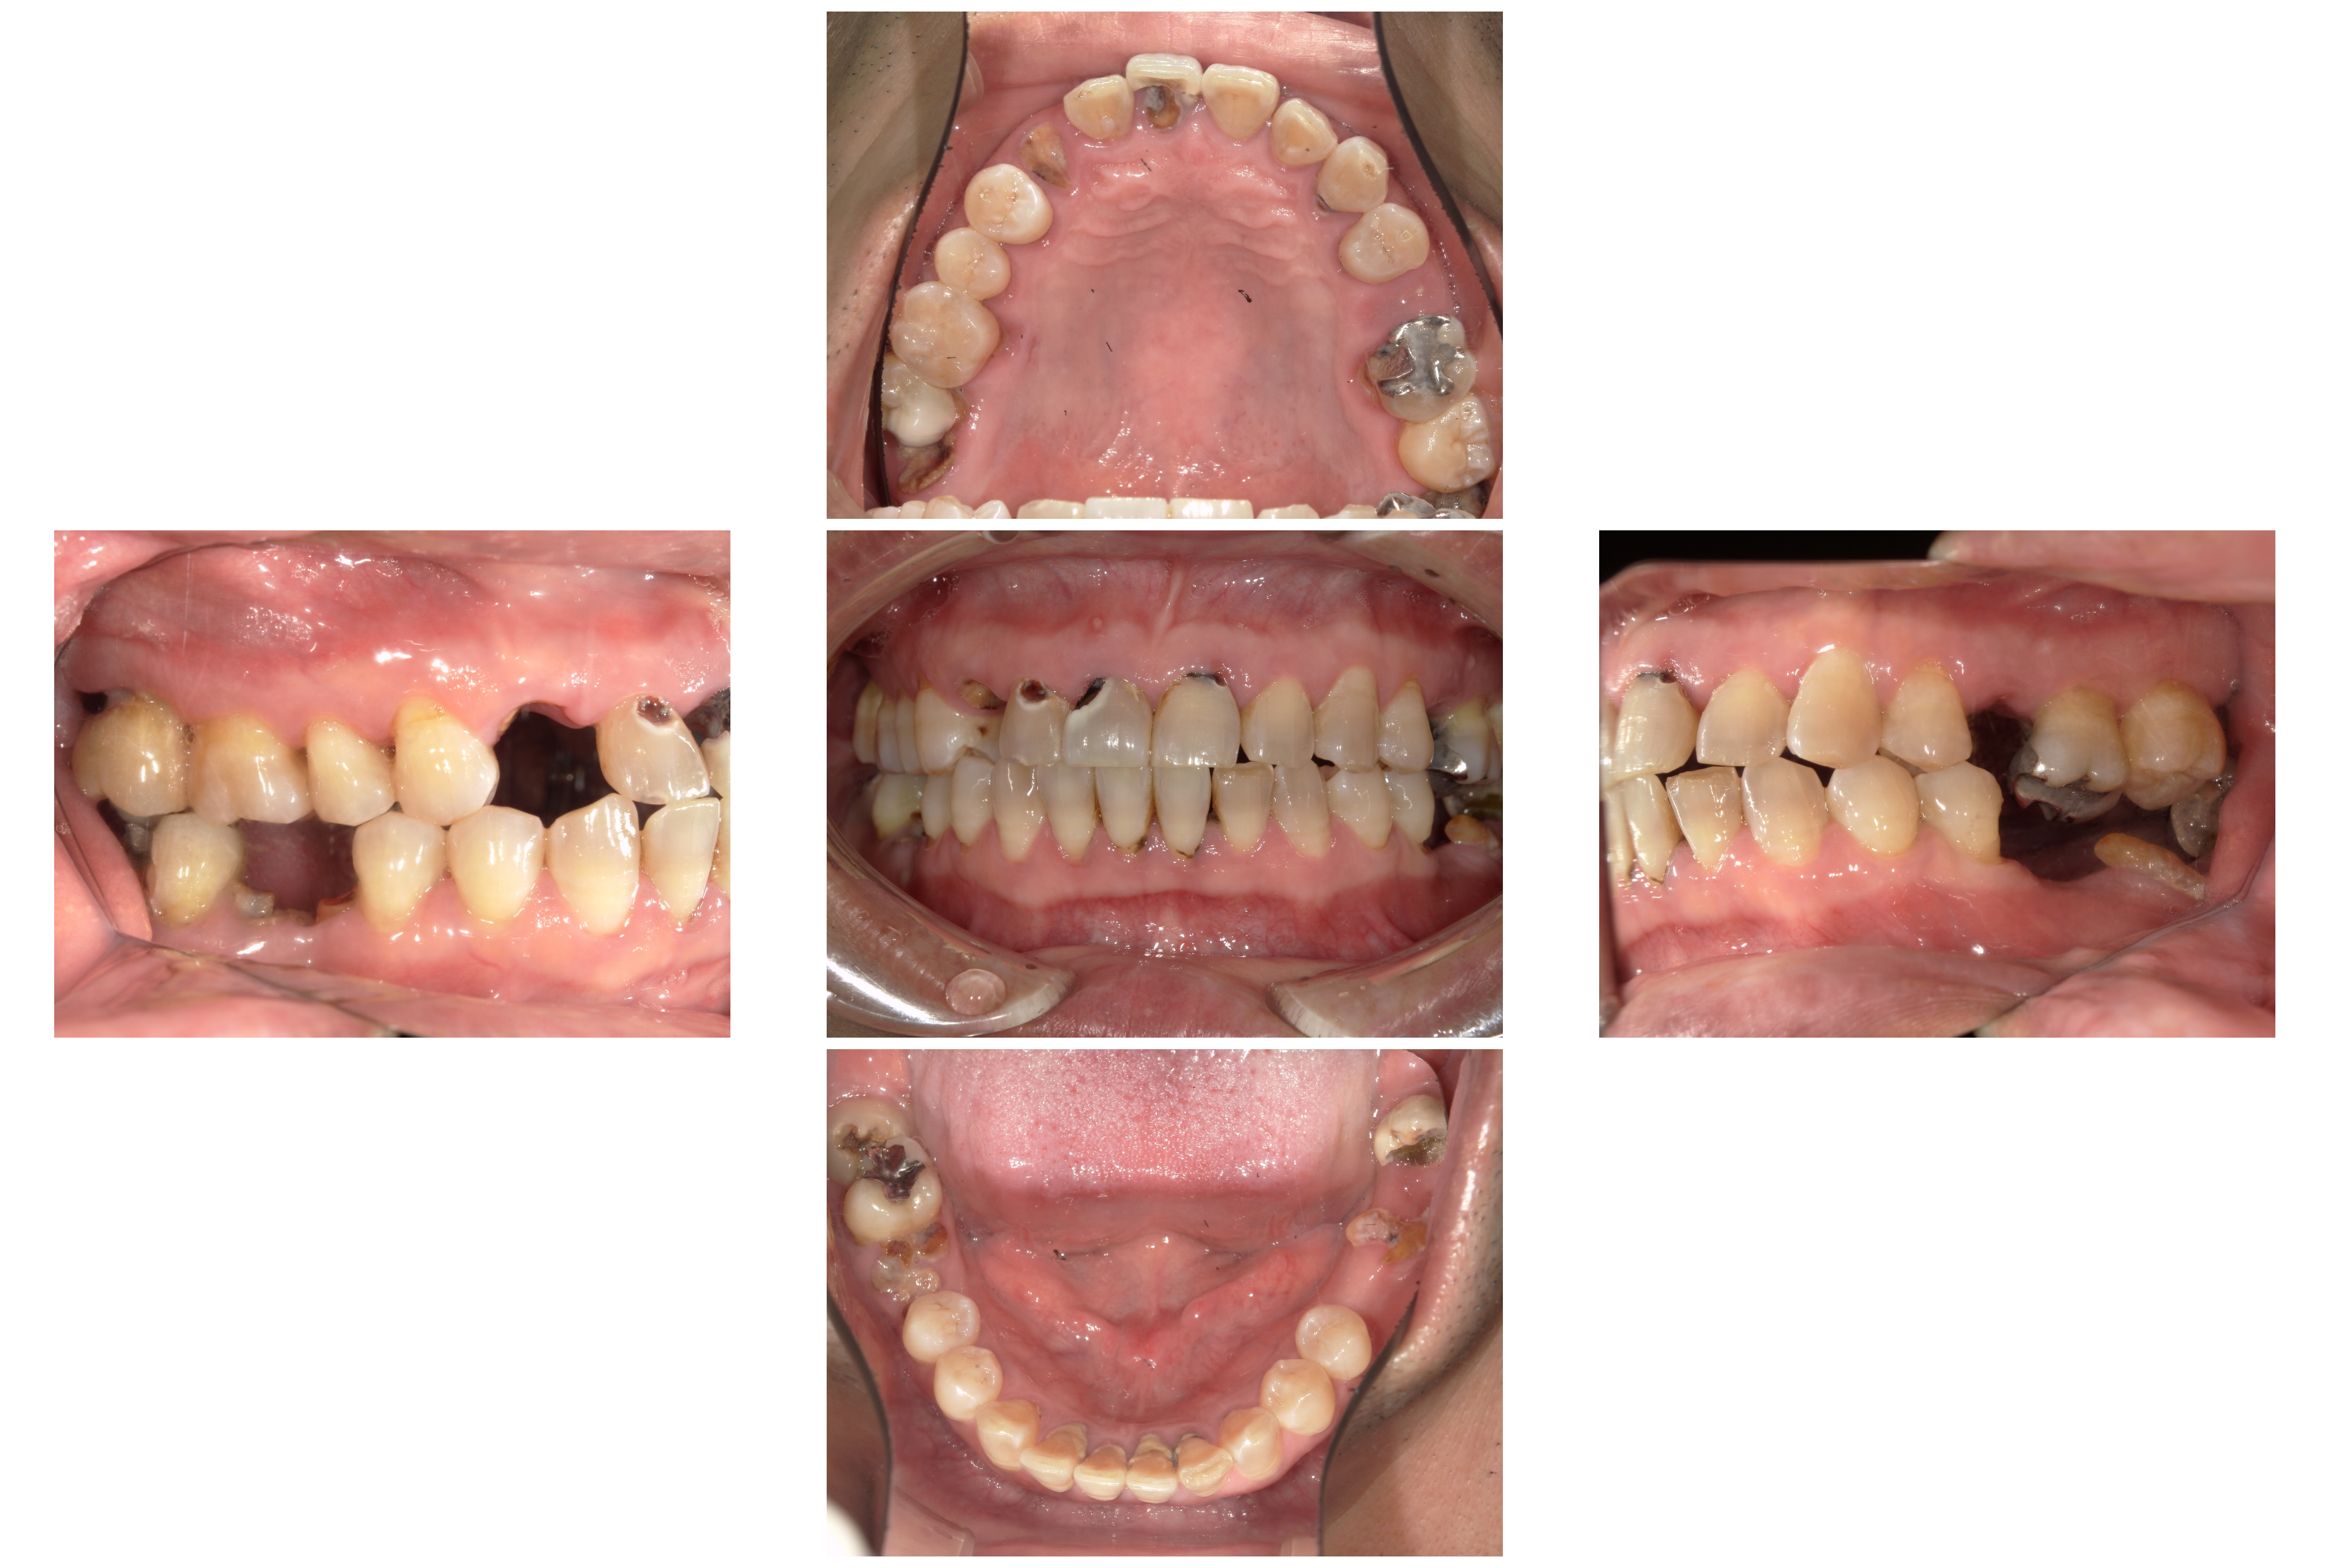

保存が難しい歯をすべて抜歯し、欠損したところは

・右上の前歯をインプラント

・下の両奥歯を義歯

・左上はブリッジ

のコンビネーションで修復しました。

術後

下の奥歯は義歯を使用して頂いています。(写真には写っていません)

治療期間:約2年